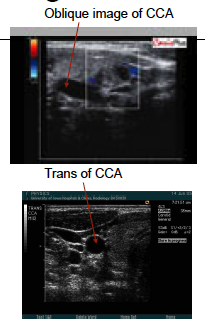

If image is oblique and you want a transverse, you must ____the transducer.

“turn”

From the ______ window you can not get the “Y”.

You will need to image the ICA and ECA separately.

moving to the _____ aproach for the longitudinal images will demonstrate the “Y” view.

anterior

lateral